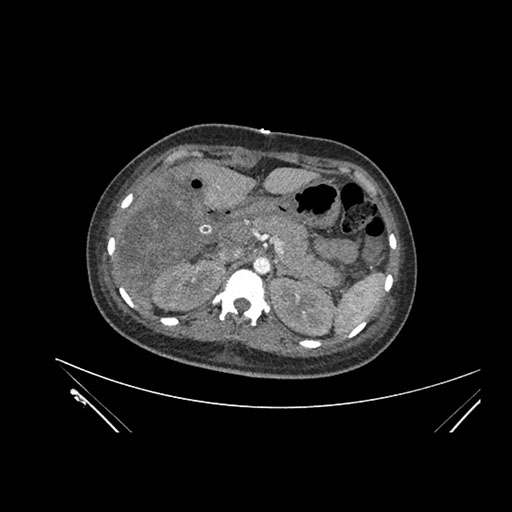

Axial Arterial

Axial Venous

Imaging analysis

Based on initial findings, which issue(s) would you be most concerned about?